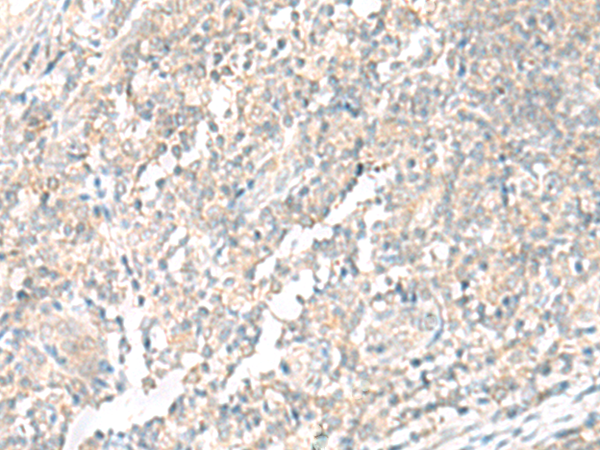

分类: 科研抗体货号: P13569别名: HEXO; THEX1; 3'HEXO应用: IHC反应种属: Human, Mouse, Rat